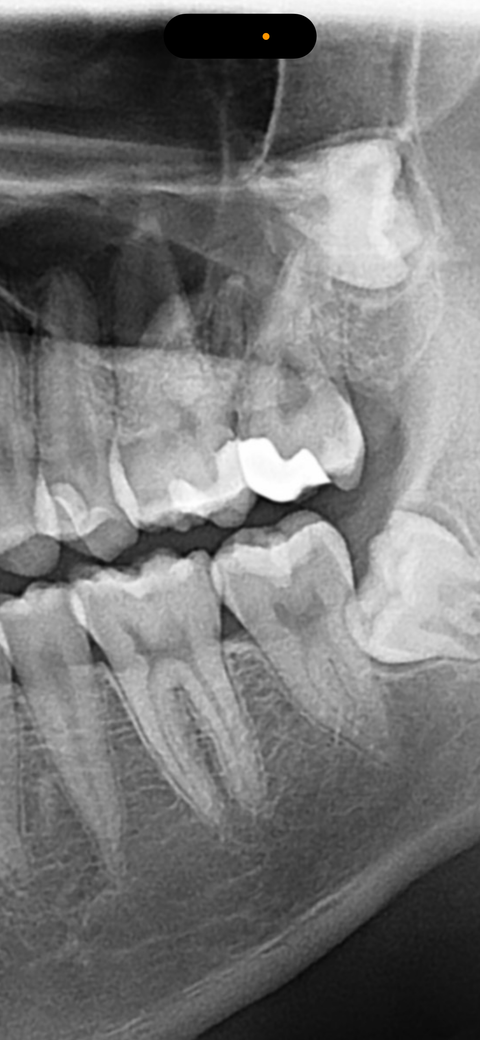

엑스레이 상으로 신경치료 가능성 높은가요?

윗 어금니 인접면에 충치가 있는것 같은데 혹시 신경치료 가능성이 높은가요? 치과에서 여쭤보질 못했네요.. 통증은 없는 상태입니다.

인접면 충치는 파노라마로 명확히 진단을 하기는 어렵습니다. 충치를 삭제해봐야 알 수 있습니다.

일단은 최대한 신경치료를 안하는 방향으로 치료를 하겟지만 충치가 깊은곳에 잇어서 신경치료 가능성도 있을것같습니다.

신경이랑 근접해 있기 때문에 신경치료 가능성이 꽤 있습니다 일단 기존 수복물 제거 후, 충치제거 후 재평가를 해봐야 할 것 같습니다

충치가 깊게 진행되어 치아의 중심부인 신경까지 영향을 미치면, 신경 치료가 필요할 수 있습니다. 통증이 없는 경우 신경에 영향을 미쳤을 가능성은 낮기에 우선은 더 지켜보고, 만약 통증 발생시에는 바로 치과 진료를 받길 권합니다.